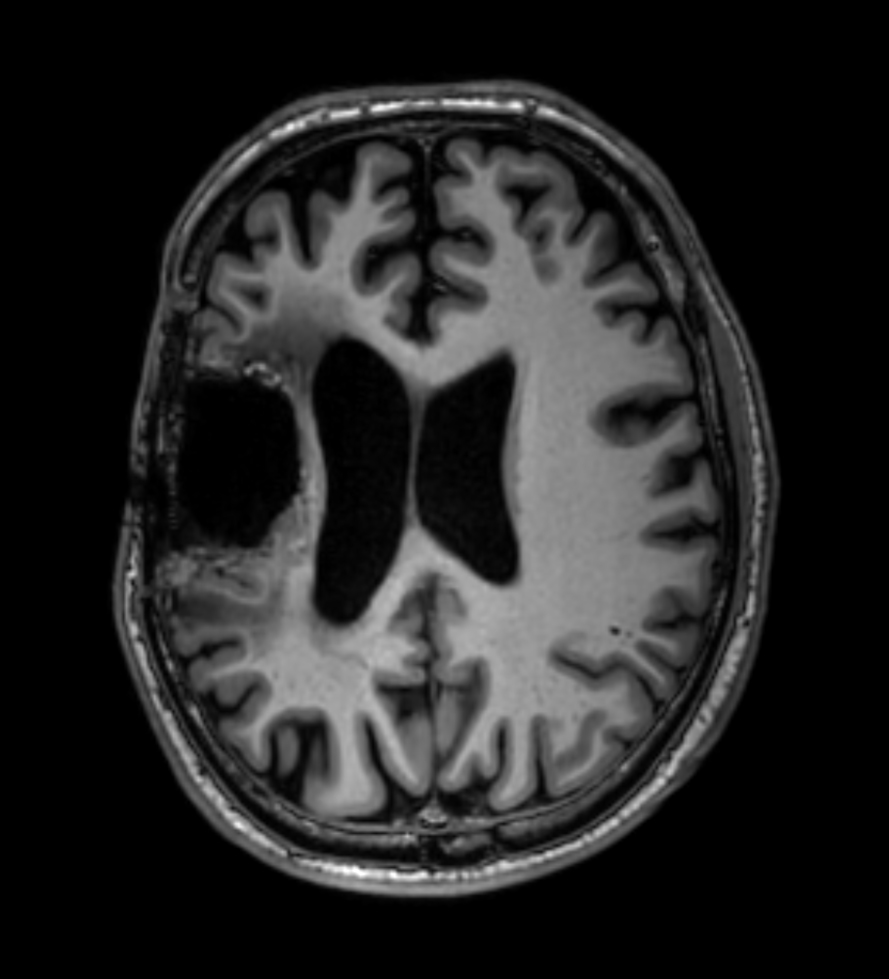

Brain glioblastoma, post-operative

Patient who was operated on glioblastoma

Sagittal 3D T1w TFE

-

3D T1w TFE - Coronal reformat

3D T1w TFE - Axial reformat